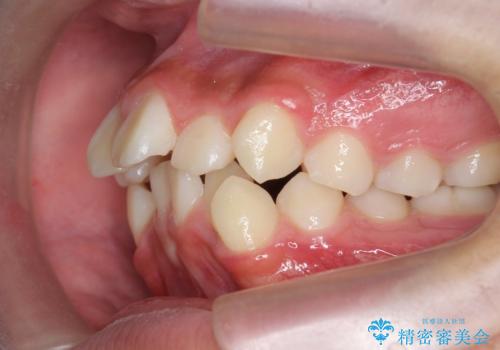

がちゃがちゃした前歯をきれいにしたい

- 前歯のがたつきが原因で歯ブラシしづらい、見た目を改善したい!と矯正治療を希望され来院されました。

スペースの不足が見られるため、小臼歯の4本抜歯を行いマルチブラケットを用いた矯正治療を計画します。

噛み締めが強く、治療に時間がかかりましたが矯正治療の仕上がりに満足いただくことができました。